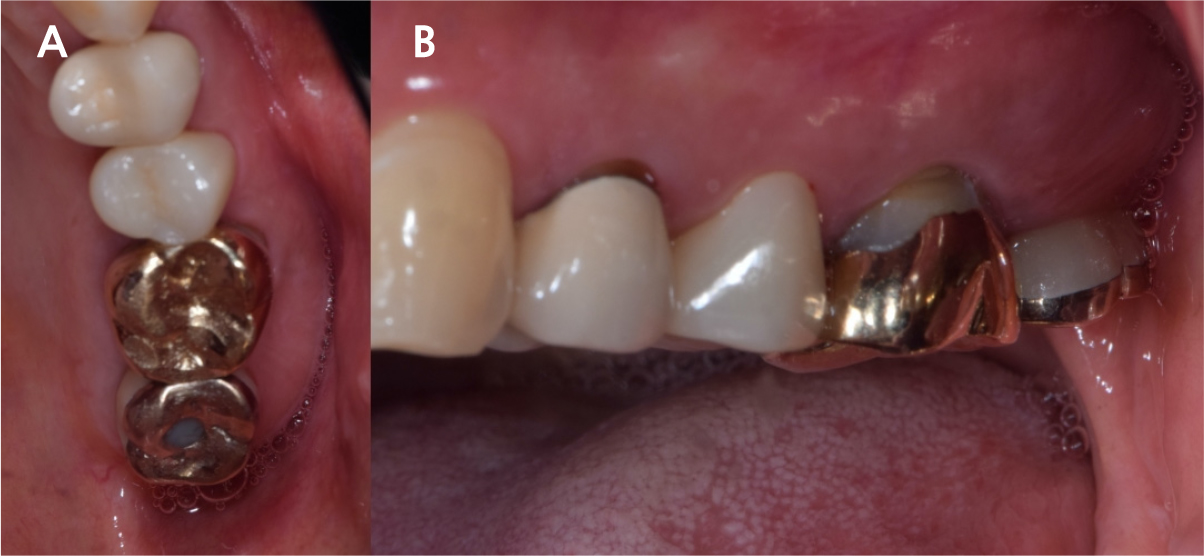

After 4 months of the first surgery, the ISQ value was 71, showing favorable stability, the prosthesis was placed consecutively, and healing progress was observed (Fig. 8A, 8B). After 5 months, the final prosthesis was completed (Fig. 9A, 9B). Supported treatment was initiated and radiographs were taken after 6 months (Figs. 10, 11, 12). In the radiograph analysis, the alveolar bone surrounding the dental implant was stable, with ossified bone verified. In a 6-month interval, the supported treatment was conducted in April 2022, showing no signs of peri-implant gingivitis or bone resorption (Figs. 13 and 14).